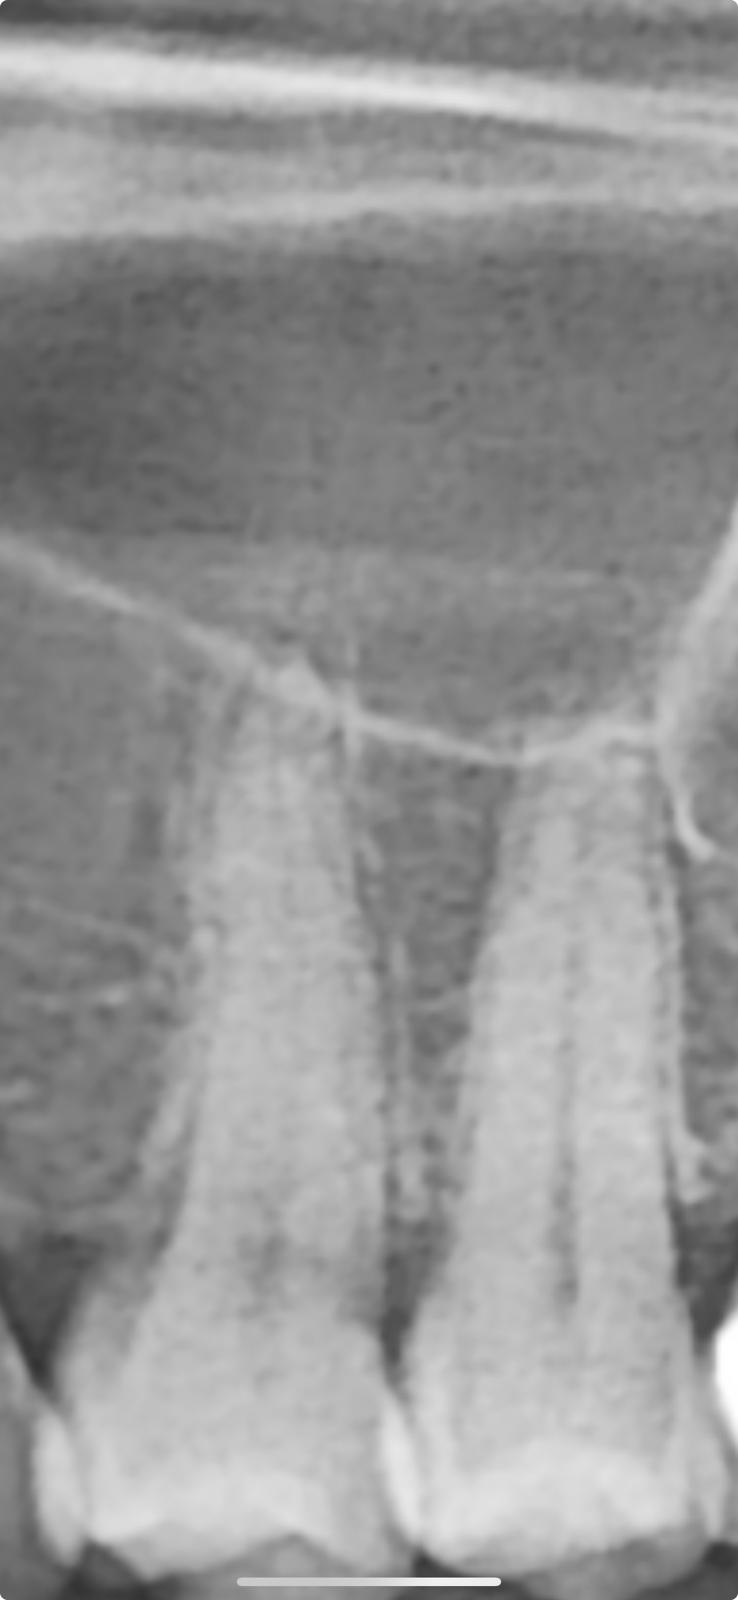

sehe einen leichten spiegel, ist vermutlich ein artefakt, da keine dynamik zu sehen ist (wenn es sich um 2 verschiedene röntgenaufnahmen zu unterschiedlichen zeiten handeln sollte).

wenn nicht, dann einfach in ein paar monaten nochmals ein röntgen machen.